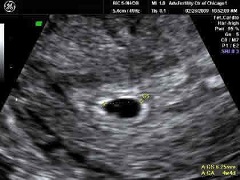

Размер плода на 5 неделе беременности - 5-6 ммНа 5 неделе беременности очередная менструация не приходит в срок. Тест на беременность будет чаще всего положительным. Современные тестовые системы реагируют на минимальные количества гормона хорионического гонадотропина в моче, и могут показывать две полоски уже после первого дня задержки менструации.

На УЗИ на 5 неделе беременности хорошо видно плодное яйцо, прикрепленное к стенке матки. Размеры его вместе с окружающими плодными оболочками и водами составляют около 1 см. При проведении УЗИ на 5 неделе беременности с применением аппаратов экспертного класса можно заметить первые сердечные сокращения, подтверждающие то, что зародыш живет и развивается.